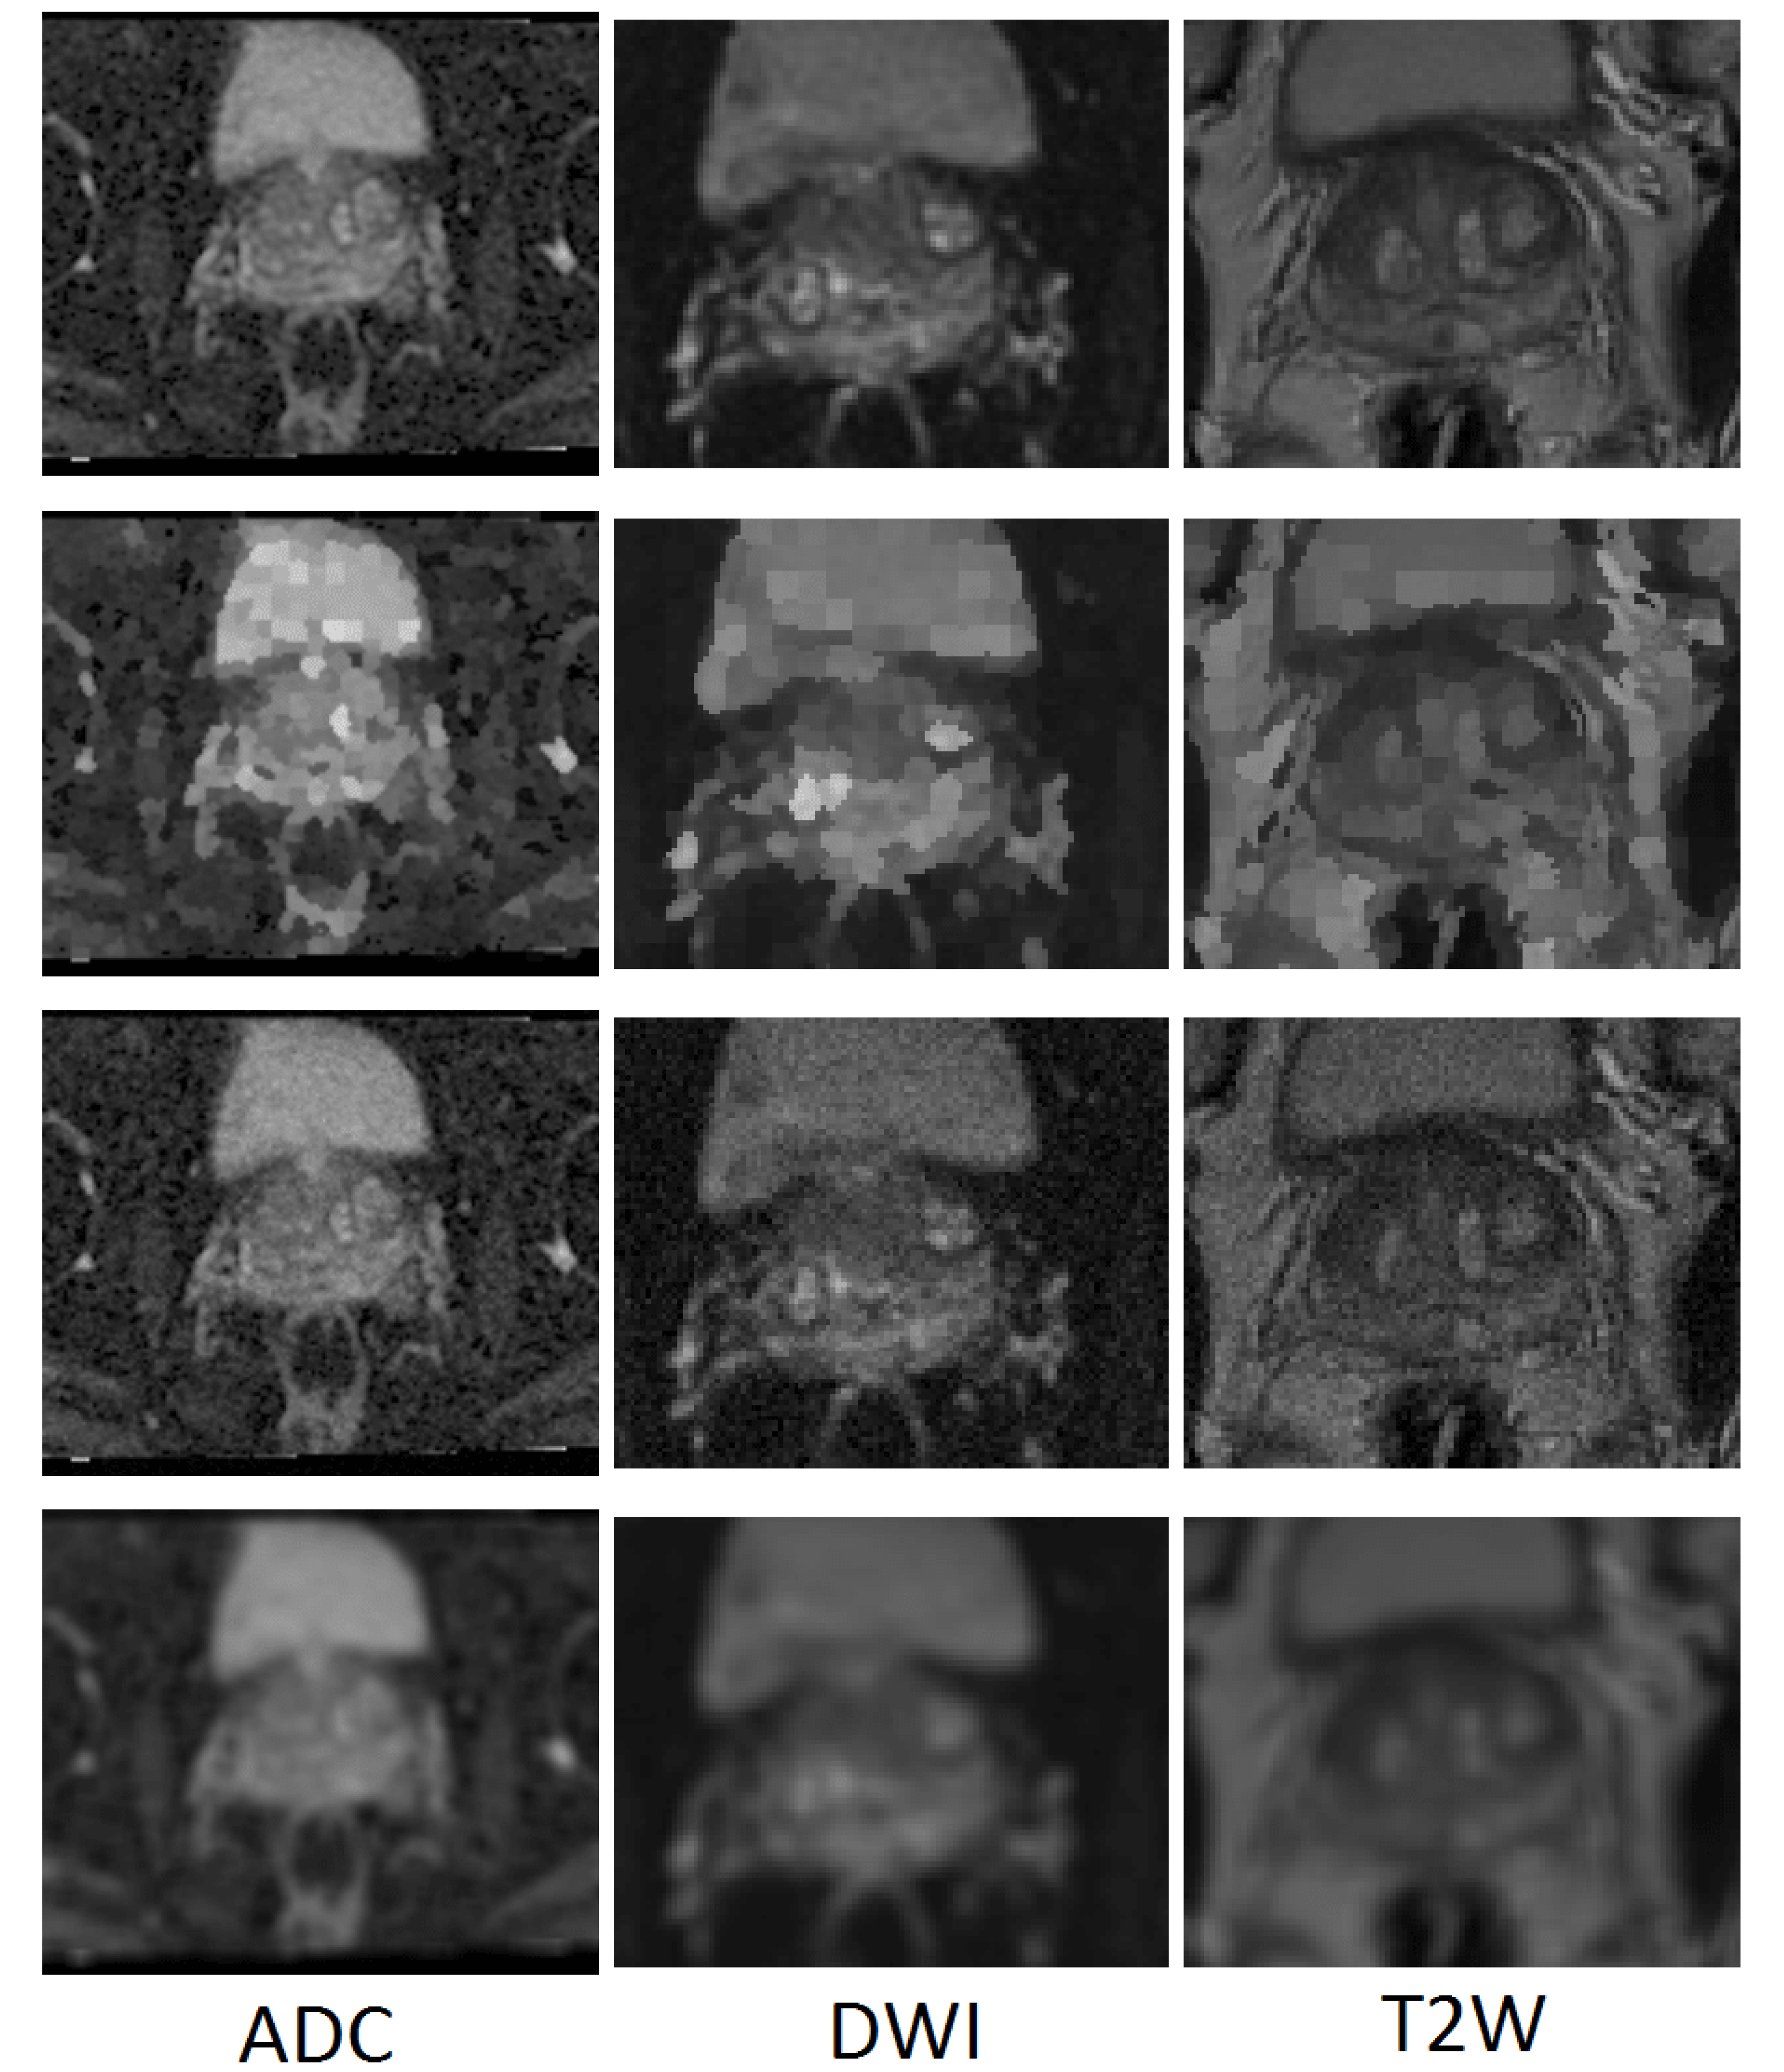

In terms of the T2W modality, similar outcome was achieved with regards to the training samples used during learning procedure for the cGAN model. The combination of raw and GNA was the best in the cGAN model; while the combination of raw and SP obtained the best output results in the cycleGAN model. To justify this by investigating the T2W modality images, we observed that the images in this modality show anatomy, especially the peri-prostatic structures, more clearly than other modalities. Figure 6 shows that ADC and DWI images have low signal around the prostate compared to the T2W modality. Superpixelizing the T2W images groups the pixels better and makes the surrounding anatomy more visible for the cycleGAN network. In the cycleGAN model there are two different domains and there is no paired input-output relation between them. The generators are penalized by the adversarial loss with the cycle consistency loss, which forces the generators to not only do the segmentation but also synthesize the original MR image from the created mask back again. As a result, the network learns a mapping between the training images and their masks and vice versa. Therefore, for the SP approach, learning is more optimised. When we compare the results of the raw plus SP images on the three modalities in the cycleGAN model, it is also consistent with this result that training using the T2W modality images obtained the best results (with DSC values of 0.748) while the DSC outcomes for DWI and ADC modalities were 0.702 and 0.710, respectively. For the DWI modality, the best results for the cGAN and cycleGAN models were achieved by using the raw plus MM images as the training set. The MM approach removes the unnecessary details from an image helping the network to focus on prostate tissue as the target part of the image during the training process. It shows consistent results with regards to the three evaluation metrics. The ROC curves and AUC values for these networks, applied to three modalities (ADC, DWI and T2W), are shown in Figure 7.

Figure 6.

Some examples of T2W, ADC and DWI MR images from our dataset, which demonstrates that DWI and ADC modalities have lower signal around the prostate compared to the T2W modality. Scaled images are shown in Figure A2 for better visualisation.

Figure A2.

Some examples of T2W, ADC and DWI MR images from our dataset, which demonstrates that DWI and ADC modalities have lower signal around the prostate compared to the T2W modality.